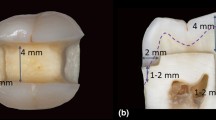

Scanning electron microscopy

The upper part of the restoration in the “SDR-bulk” group showed large shrinkage vectors without a preferred direction. In the lower part of the restoration, many small shrinkage vectors pointed toward one side of the cavity (Fig. 4a–b). The scanning electron microscopy (SEM) images showed debonding at one side of the margin and part of the floor (Fig. 4c–d), whereas other locations had an intact bond (Fig. 4e–f).

Shrinkage vector field of the “SDR-bulk” restoration with the a x-plane and b y-plane of the micro-CT scan in the background. Glyphs (or arrows) were scaled by a factor of 5 to enhance visibility. Small shrinkage vectors are seen at the lower restoration part pointing toward one side (right side) away from the location of the first debonding (left side). The SEM images (× 200 magnification) show c debonding at one margin (left) and d part of the cavity floor (arrows), whereas an intact bond was seen at e another part of the floor of the restoration and f the enamel margin (right). The star indicates a representative traceable glass bead

In the upper part of the first increment “SDR-increment1,” the shrinkage vectors pointed downward toward the cavity floor, whereas the shrinkage vectors showed irregular arrangement in the lower part, in which only a few vectors pointed upward toward the curing light (Fig. 5a–b). In the second increment “SDR-increment2,” some shrinkage vectors pointed downward and some shrinkage vectors pointed sideways. The underlying first increment “SDR-increment1-covered,” which is the lower part of the whole restoration, displayed many small vectors pointing upward away from the cavity floor (Fig. 5c–d). The SEM images showed intact cavity margins and some debonding at the cavity floor but to a lesser degree than in the bulk application “SDR-bulk” (Fig. 5e–h).

Shrinkage vector field of the “SDR-incremental” restoration with the a,c x-plane, b y-plane, and d z-plane of the micro-CT scan in the background. Glyphs (or arrows) were scaled by a factor of 5 to enhance visibility. “SDR-increment1” and “SDR-increment1&2” showed random movement of the shrinkage vectors with shrinkage vectors near the free surface showing downward movement. SEM images (× 200 magnification) display e,h intact bonds at both enamel margins and f,g debonding at the floor of the restoration (arrows). The star marks a traceable glass bead

“EvoFlow-incremental” group

In the first increment “EvoFlow-increment1,” the shrinkage vectors pointed upward and away from the cavity floor and then clearly deviated toward one side of the cavity. In the upper part of “EvoFlow-increment1,” small shrinkage vectors pointed downward, as shown in Fig. 6a–b. In the second increment “EvoFlow-increment2,” large shrinkage vectors pointed downward, whereas many very small vectors pointing away from the cavity floor were observed in the lower part of the restoration “EvoFlow-increment1-covered” (Fig. 6c–d). The SEM images displayed an intact bond on one side of the enamel margin (Fig. 6e), whereas debonding was observed in the other side of the enamel margin and along the cavity walls and the floor (Fig. 6f–h).

a, b Shrinkage vector field in the “EvoFlow-incremental” group, which showed large shrinkage vectors at the lower part of “EvoFlow-increment1” and small shrinkage vectors pointing downward at the free surface. c,d In “EvoFlow-increment1&2,” large shrinkage vectors pointed downward at the free surface of the restoration, whereas the remaining restoration displayed small shrinkage vectors with upward direction. SEM images (× 200 magnification) displayed an e intact bond on one side of the enamel margin, whereas the other side showed some areas of debonding f along the floor and g,h cavity walls (arrows). The star indicates a traceable embedded glass bead

The tooth-composite interface is the other influencing factor of the anisotropic shrinkage pattern resulting in debonding and gap formation due to compensatory mass movement through stress relaxation [48]. Although studying interfacial gaps on micro-CT scans was beyond the scope of the current research, some gaps were observed in the SEM images at the same site as the shrinkage vector origin. SEM was used as one representative sample of each study group for an adjunctive comparative evaluation. However, gap formation might occur upon sample sectioning and/or due to the effect of the high vacuum needed for SEM observation [54]. This constitutes a limitation of the study considering that the analysis was not performed on replicas and that a very good bonding system (Optibond FL) was used. Thus, a nondestructive evaluation of gaps using micro-CT scans would be advantageous [55].